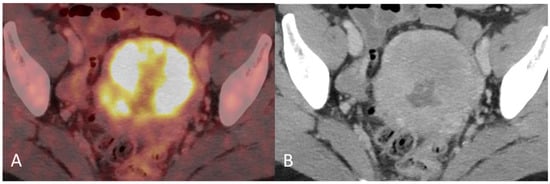

Figure 2. (A) Baseline axial PET/CT fused image. The metabolic activity is inhomogeneous, with areas of high to low metabolic activity. (B) Contrast-enhanced axial CT shows an enlarged uterus with endometrial thickening and polypoid tumour masses protruding into the uterine cavity. The tumor appears hypodense to the myometrium with signs of myometrial invasion. There was no involvement of the ovaries, fallopian tubes or cervix on either the PET or CT.